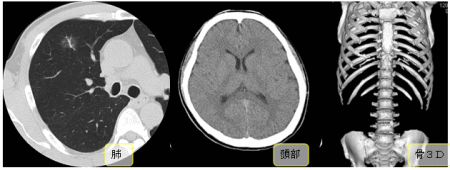

造影剤等薬剤を使用しないで撮影を行います。頭部や胸腹部を撮影することが多いです。また、骨折等の状態を確認するのにレントゲン写真で分かりにくい場合は、骨の3DCTを撮影することもあります(画像は左から 肺、頭部、骨3D)